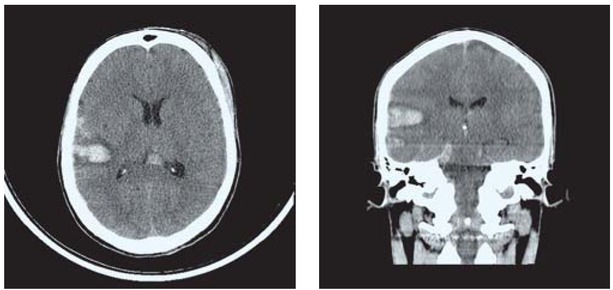

The patient was admitted to the neuro ICU for further treatment. A CT scan revealed right parietal contusion, quadrigeminal cistern, fourth ventricular haemorrhage, and no significant mass effect or hydrocephalus (Figure 1). Thus, the patient was diagnosed with a moderate head injury.

Figure 1

CT scan showing right parietal contusion, quadrigeminal cistern and fourth ventricular haemorrhage.